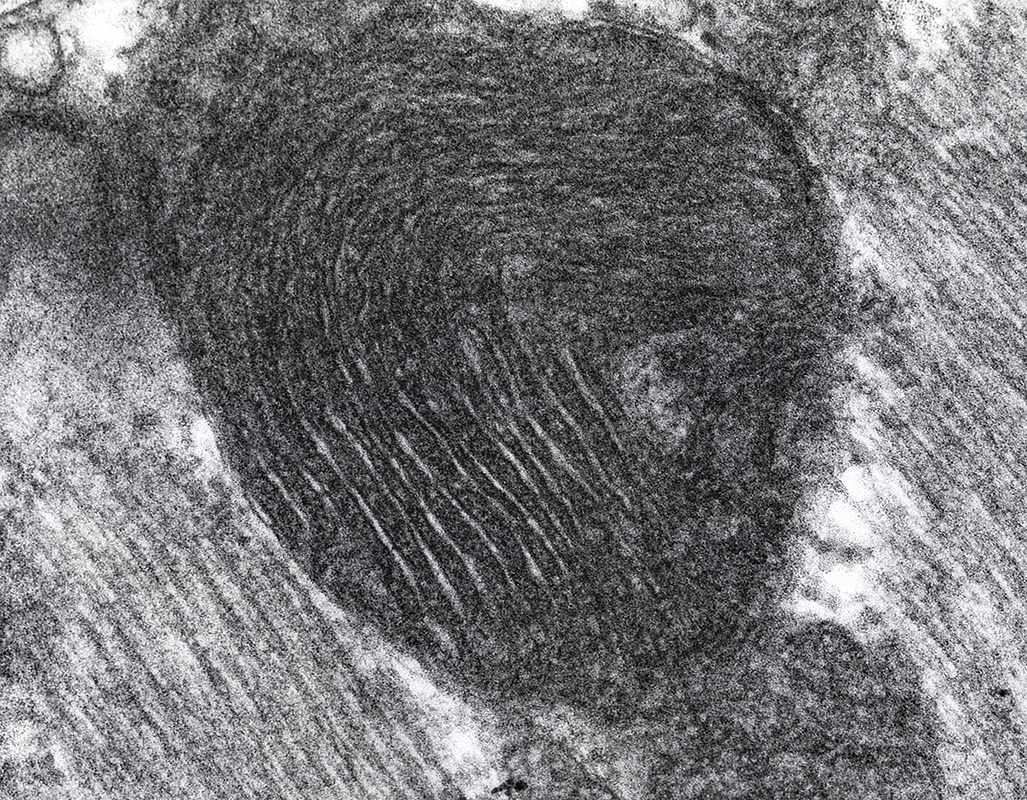

Mitochondrial Infantile Encephalopathy, Ultrastructure

Mitochondria

Proliferation

Shapes & structure: Irregular

Sizes: Often large

Lipid droplets

Scattered in muscle fibers